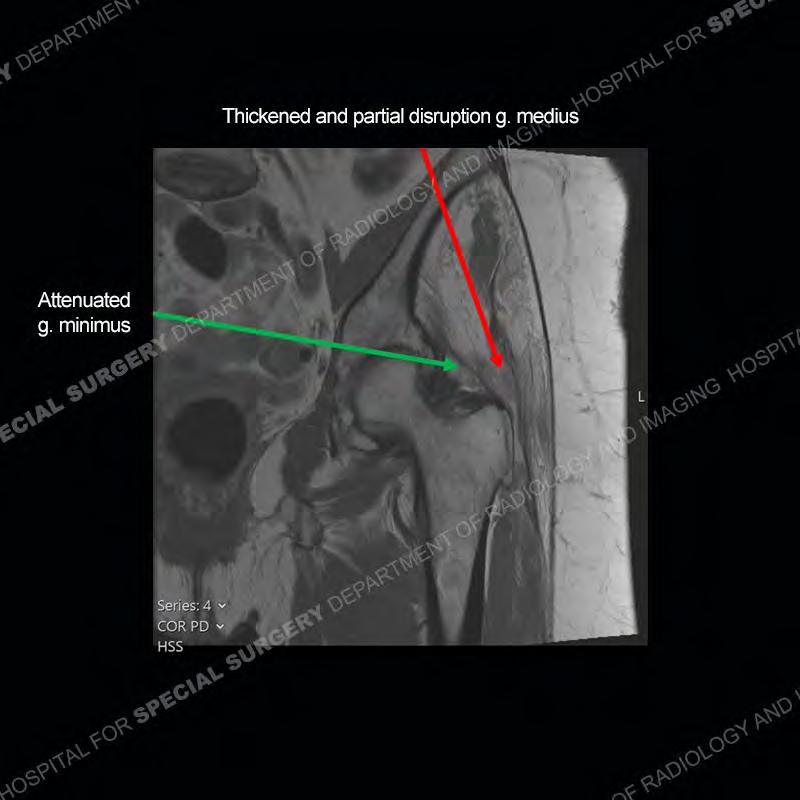

The radiograph is not particularly contributory in this case. The MRI demonstrates markedly abnormal architecture of the gluteus minimus and anterolateral band of the gluteus medius. Portions of the tendons are high signal, portions are highly attenuated, and portions are disrupted. A large, complex fluid collection is present in the adjacent soft tissue.

Diagnosis: Gluteal Tendinosis and Disruption with Complex Trochanteric Bursal Collection

Not as much of a diagnostic dilemma as many of the other cases shown but just a nice example of the pathology seen of the gluteal tendons and a cause of trochanteric pain. Although, frequently thought of in isolation, trochanteric bursitis or bursal thickening is much more commonly a reactive change to underlying pathology of the subjacent gluteal tendons. The gluteus medius is divided into a posterior band and an anterolateral band. Tendinosis and partial tearing very commonly will involve the gluteus minimus and especially the more posterior fibers and then propagate into the anterior lateral band of the gluteus medius. Involvement of the posterior band of the medius is much less common and engenders a marked degree of functional impairment.